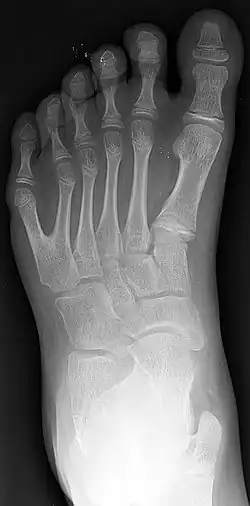

Röntgenfoto van een voet met 6 tenen (polydactylie)

- Polydactylie